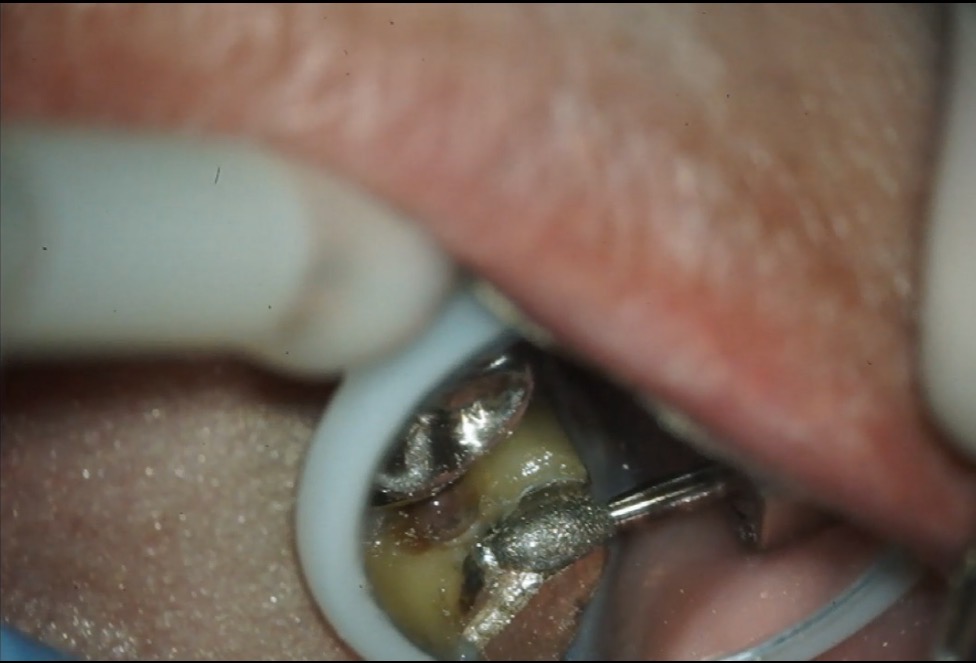

精密根管治療→根管充填 左上7

過去に根管治療が施されている歯になります。

痛みが出現したため、再根管治療を行いました。

精密根管治療

根管充填